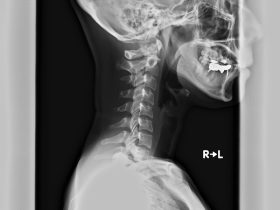

「ストレートネックが治らない原因と診断及び治し方」 ストレートネックとは 首の正常な曲線は、通常レントゲン写真の側面から見た時、17㎝の半円を描いた前彎の曲線の位置になければなりません。 主な原因には、長時間の… -